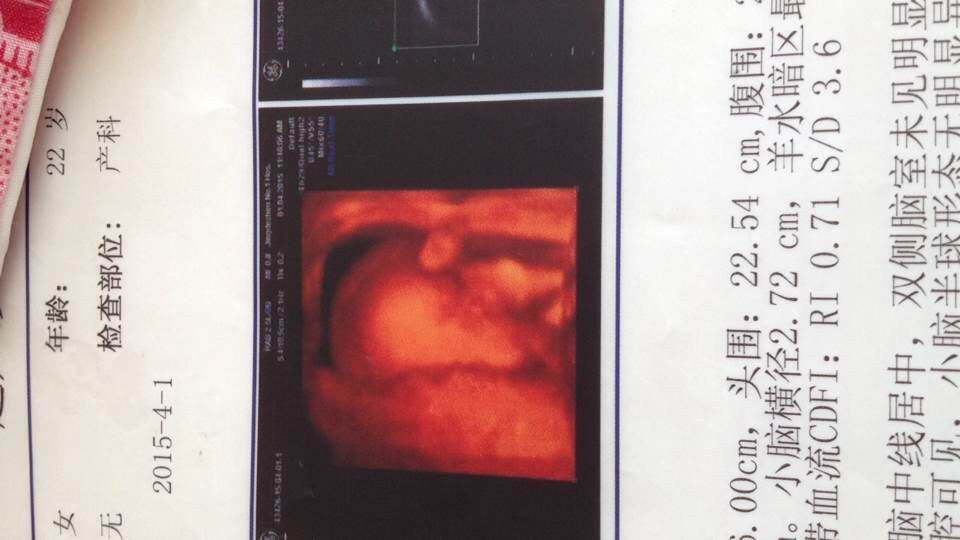

如何从b超单看胎儿性别?胎儿的性别一直是爸爸妈妈比较关心的问题,可是现在医院已经不允许医生告诉父母胎儿的性别了。那么,我们是不是就没有办法知道了呢?没关系,我们可以自己看b超单哦! 在怀孕16周左右做b超,就可以了解胎儿生长发育大体情况了。小编现在就跟大家分享一下如何从b超单看胎儿性别。首先,我要跟爸爸妈妈们普及几个专业名词。 GS是胎囊,也叫孕囊,是怀孕最初胚胎的形态。FE是胎芽,也就是早期胎儿。CRL是胎儿头与臂之间的距离,表示胎体纵轴平行测量最大的长轴,主要用于判定孕7-12周的胎龄。FH是胎头,轮廓完整为正常。BDP是胎头双顶径胎儿头部左右两侧之间最宽部位的长度,又称为“头部大横径”。H是胎心。FL是股骨长度。FM是胎动。PL是胎盘。AMN是羊水。TCD是小脑横径。HC是头围。AC是腹围。FTH是胎儿退步皮下脂肪厚度。 其一:看数据,如果长和宽的相差在一倍生径以上男宝宝可能性大。长和宽相等女宝宝可能性大。 其二:看形状,像茄子或长条状的是男宝宝可能性大,圆圆的是女宝宝可能性大。 1、7W+1D的BC数据 胎囊2.9 1.9 生的是男孩 2、9W+4D的BC数据: 宫内见46.630.2mm孕囊 双胞胎都是女孩 3、60天的BC数据: 孕囊大小是3.6 1.6MM 生下的是帅哥 4、5W+6D。孕囊:25mm11mm 男孩 5、数据:胚囊:23×17×16 生下的是小美女 6、46天BC数据孕囊:201717 女孩 7、7w+1D的BC结果:3220mm妊娠囊 女孩 8、8周时是 1.6×1.7 生下的是千金 9、8周的时候是4128MM 生下的也是女宝宝 10、8周多是的BC,胎囊是19MM10MM 后来BC照出来也是男宝宝 其实,B超医师经验越丰富,B超扫描仪器的质量越高,B超看胎儿性别的准确性就越高。但是,就连最好的B超医师通常也无法百分之百地肯定,你怀的到底是男孩还是女孩。而且,你需要知道的是,在中国大陆,非医学原因的训队胎儿性别鉴定是被明令禁止的。 有人说,不光有b超单看胎儿性别这个方法,在我国自古以来民间就流传着判断胎儿性别的小技巧,他们认为孕妇口味如果与前胎不同,则胎儿的性别也会改变。一般认为胎心较强较慢的话,胎儿是男孩的可能性较大;反之则是女孩。不过,其实这些都没有什么科学依据的,妈宝叹坊妈们不要轻易相信哦,否则会白白失望或者空欢喜一场。